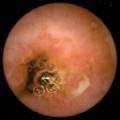

Sillon scabieux au dermoscope

GALE

SARCOPTE SCABIEI

DERMOSCOPIE